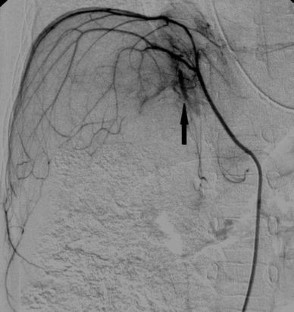

Five boys and three girls (mean age 15.2 months) were treated with preoperative TACE combined with systemic chemotherapy for unresectable hepatoblastomas. Mean tumor diameter and mean alfa-fetoprotein (AFP) level were 11.8 cm and 549,386 ng/mL, respectively. Pretreatment, the extent of disease (PRETEXT) was: II, 1; III, 6; IV, 1. For all patients, preoperative systemic chemotherapy was administered before TACE. At each TACE, carboplatin and adriamycin mixed with iodized oil were infused into the feeding arteries. Tumor response and prognosis after treatment were evaluated.

TACE resulted in few Grade 1 adverse effects (AEs), without G3 or more AEs, according to CTACAE 3.0. Mean tumor shrinkage was 60.9 %, and the mean AFP decrease from initial levels was 94.8 %. In all cases TACE combined with systemic chemotherapy enabled subsequent safe and complete surgical resection. After a mean follow-up of 59 months, tumor-free survival was 75 %.

Fig. 1

Fig. 2